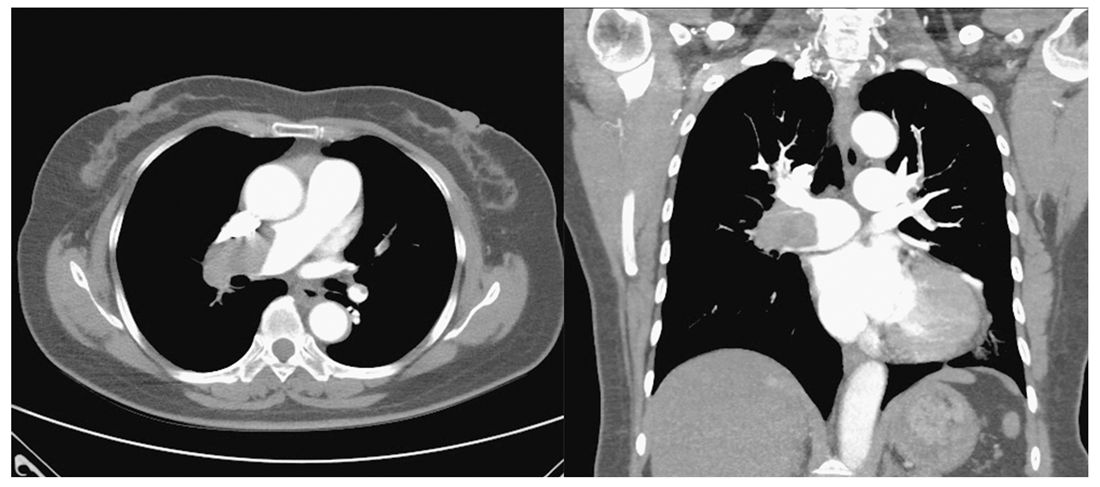

Pulmonary Embolism and Severe Asthma: Case Report and Literature Review

2. Case Presentation